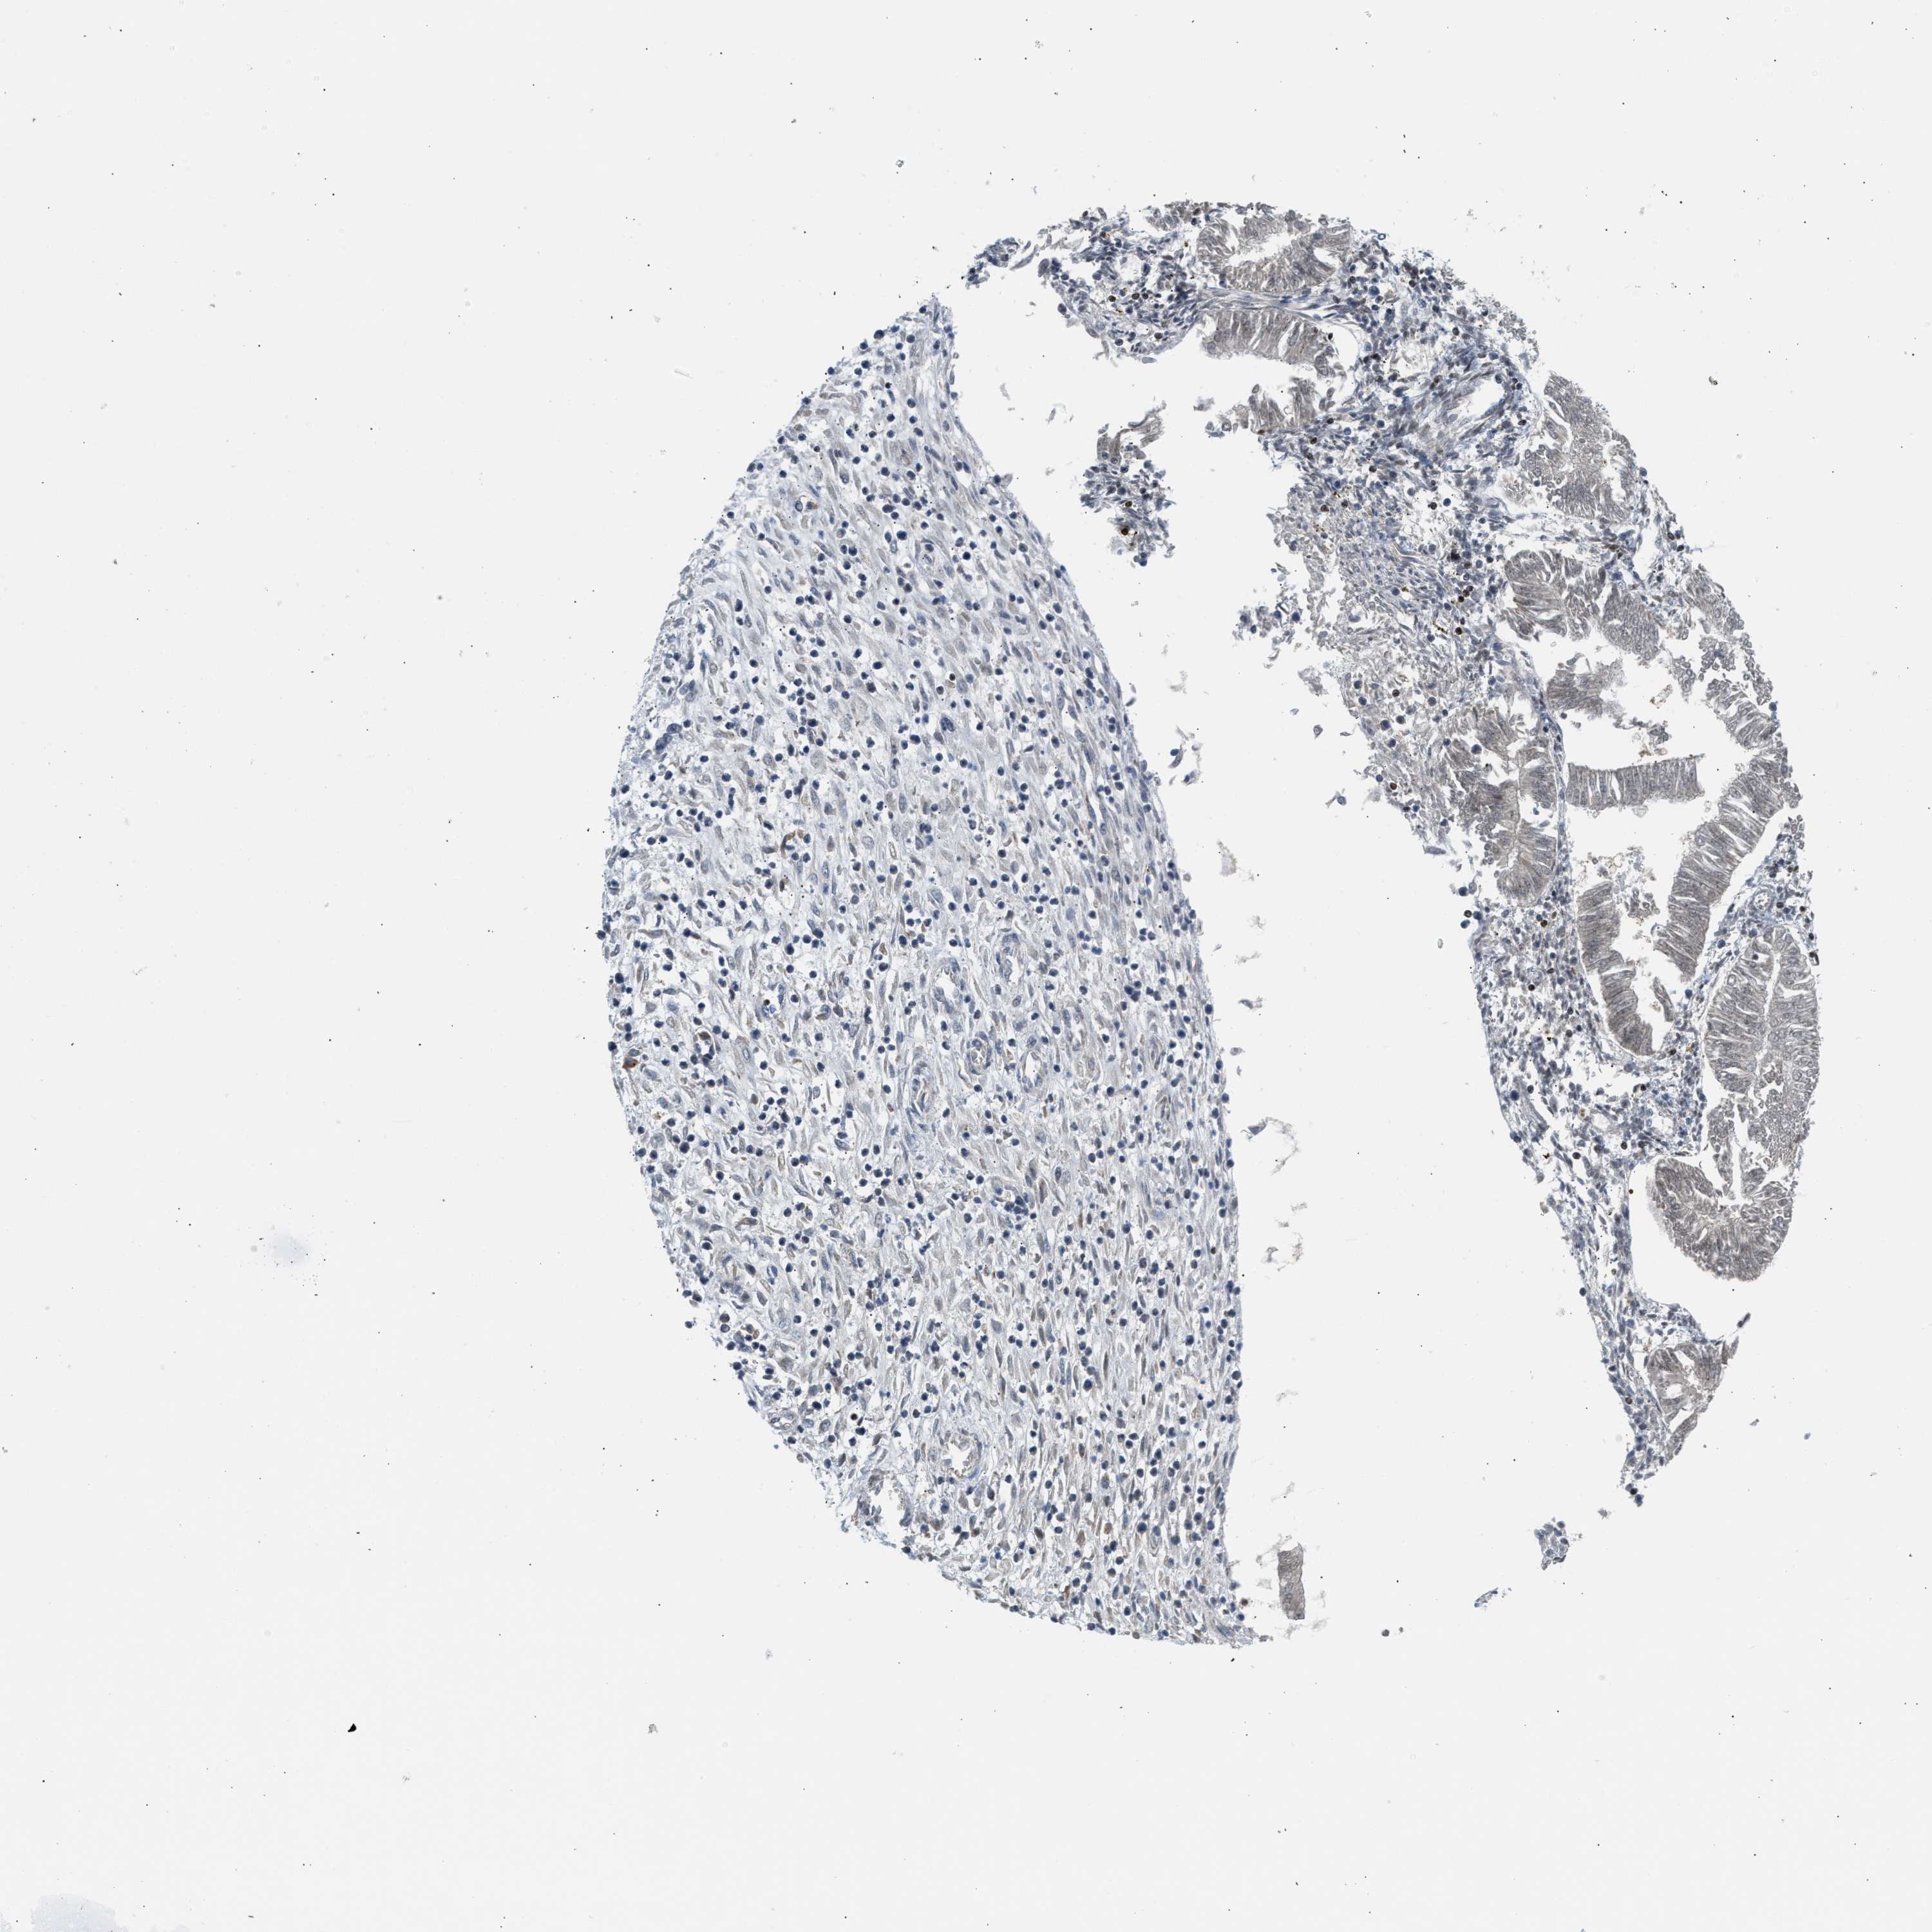

ENDOMETRIAL CANCER - Protein expressioni

A mouse-over function shows sample information and annotation data. Click on an image to view it in a full screen mode. Samples can be filtered based on level of antibody staining by selecting one or several of the following categories: high, medium, low and not detected. The assay and annotation is described here.

Note that samples used for immunohistochemistry by the Human Protein Atlas do not correspond to samples in the TCGA dataset.

Antibody stainingi

Antibody staining in the annotated cell types in the current human tissue is reported as not detected, low, medium, or high, based on conventional immunohistochemistry profiling in selected tissues. This score is based on the combination of the staining intensity and fraction of stained cells.

Each image is clickable and will lead to virtual microscopy that enables deeper exploration of all samples and also displays staining intensity scores, fraction scores and subcellular localization as well as patient and tissue information for each sample.

Antibody CAB020139

Staining

High

Medium

Low

Not detected

Intensity

Strong

Moderate

Weak

Negative

Quantity

>75%

75%-25%

<25%

None

Location

Nuclear

Cytoplasmic/membranous

Cytoplasmic/membranous,nuclear

Adenocarcinoma, NOS